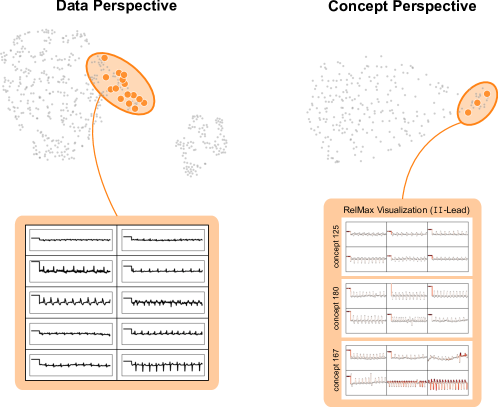

In contrast to detecting spurious samples, recent work focuses on identifying spurious model internals directly. This aligns with mechanistic interpretability, which seeks to decipher the internal mechanics of DNNs [56, 31, 13]. As outlined in Sec. 3.1, various global XAIs methods aim to explain the role of individual neurons, and these insights can be leveraged to detect spurious model internals by clustering learned concepts and identifying outliers. Given input data with samples, Pahde et al. [59] compute spatially aggregated relevances . Subsequently, they compute the pairwise cosine distance per column (i.e., channel/concept) and embed the resulting distance matrix in a low-dimensional space using dimension reduction techniques like t-Distributed Stochastic Neighbor Embedding (t-SNE) [71] or Uniform Manifold Approximation and Projection (UMAP) [49]. This low-dimensional embedding can be visualized to identify outliers through human inspection or anomaly detection algorithms, such as the Local Outlier Factor [12]. In summary, outlier representations can be identified in an embedding representation , obtained as

where reduces the dimension to , and the pairwise distance function is applied along all channel dimensions in the latent representation , either given by activations or relevance scores for layer . Note that this approach assumes over-parameterization resulting in redundant neurons, allowing to distinguish between similar and dissimilar concept representations. An example is shown in Fig. 4 (bottom), where latent relevance scores from a ResNet50 model trained for melanoma detection are used to identify outlier concepts, specifically a cluster focusing on band-aids rather than clinically relevant features. Notably, Eq. 3 can easily be extended to find outlier directions instead of neurons. Specifically, this involves a linear transformation of latent representations using the directions of interest, e.g., obtained in unsupervised manner as described in Sec. 3.1.

Results for other classes, model architectures, and datasets are presented in Appendix A.6.1. This includes experiments with ECG data in Fig. 10, revealing the artificially inserted static noise in the attacked lead from both data and model perspectives. Notably, dominant spurious concepts, such as the artificial timestamp in HyperKvasir or the static noise in PTB-XL, may not be detected as outlier concepts. In such cases, analyzing prediction sub-strategies via PCX may provide additional insights on spurious inlier behavior. Hard-to-interpret concept representations pose another challenge for the model perspective. For example, the brightness artifact in CheXpert is not clearly visible in the concept UMAP (see. Fig. 15, right), but can easily be detected using SpRAy (Fig. 15, left) or PCX (Fig. 22). In summary, while all considered spurious features are detected, the choice of bias identification approach is crucial, as some shortcuts are easier to detect as outlier concept (e.g., ruler) and others via PCX (e.g., brightness, static noise in ECG).